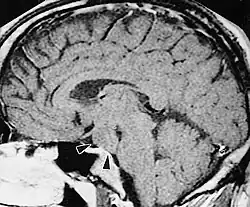

A hypothalamic hamartoma (black arrows) on MRI

The tumor is difficult to detect by CT due to decreased sensitivity of the scan at the level of the sella turcica. MRI is the primary imaging modality for detection, with the lesion being of similar signal intensity to gray matter and non-enhancing with contrast. Lack of enhancement is an important imaging characteristic to help distinguish the tumor from similar masses that can occur in this region. These include germ cell tumors, granulomas of Langerhans cell histiocytosis and hypothalamic astrocytomas, as these lesions usually demonstrate at least partial uptake of contrast.[1]